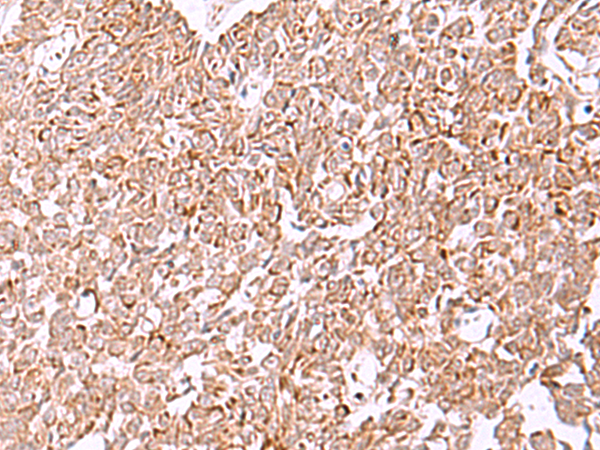

IHC positive control:

Human lung cancer and Human ovarian cancer

IHC Recommend dilution:

40-200